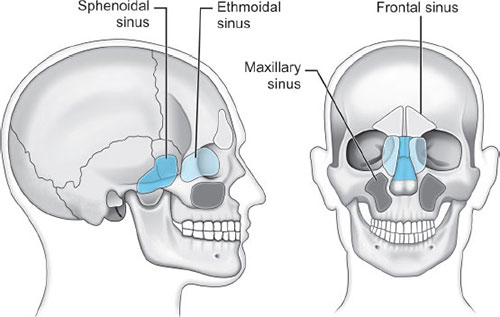

Paranasal sinuses: Sphenoid, ethmoid, maxillary, and frontal (Fig. 4).

Prolonged nasotracheal intubation has most often been associated with infection of the maxillary sinus as its drainage is hindered by the location of the ostia superiorly in the sinus promoting a chronic infectious process.